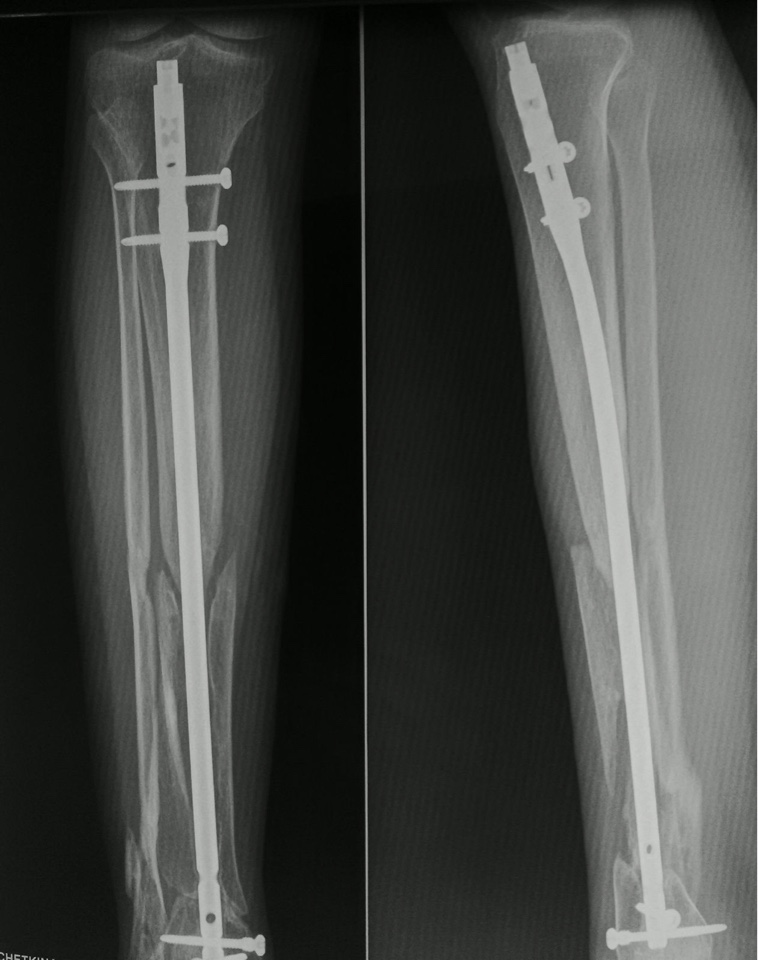

Женщина, 24 г. В июне прошлого года закрытый интрамедуллярный остеосинтез tibia (за 6 нед. до этого - открытый перелом голени после мотоаварии). На данный момент - клиника несращения. Проявлений инфекции нет. Снимки в приложении.

3 - остеотомия малоберцовой кости, устранение вальгусной деформации;

План вполне адекватный, вопрос только в технических нюансах - как собираетесь исправлять ось большеберцовой? Можно одномоментно, постпепенно, таким или другим аппаратом....

Надо добиться, чтобы стержень оказался в запланированом отделе дистального эпиметафиза большеберцовой кости.

Малоберцовую надо пересечь.

Представленный случай очень интересен с точки зрения выбранной тактики лечения, её хирургической реализации. Без детального анализа этого подходить к выбору метода лечения очень рискованно. Сейчас необходимо понять: Что произошло, и тогда станет понятно что делать? Очень интересно увидеть рентгенограммы до выполненного остеосинтеза. По имеющимся можно предположить, что выбранный стержень оказался неадекватным диаметру костномозговой полости (она на этом уровне имеет овоидную передне-заднюю форму) и поэтому стал клином который разъединил отломки вдоль оси и стал причиной диастазов в разных плоскостях. Это о механике. Биология: диастазы очень быстро заполнились рубцовой тканью. Очень стабильный остеосинтез не способствовал формированию хотя бы несколько избыточной костной мозоли. В результате атрофический многоплоскостной псевдоартроз.